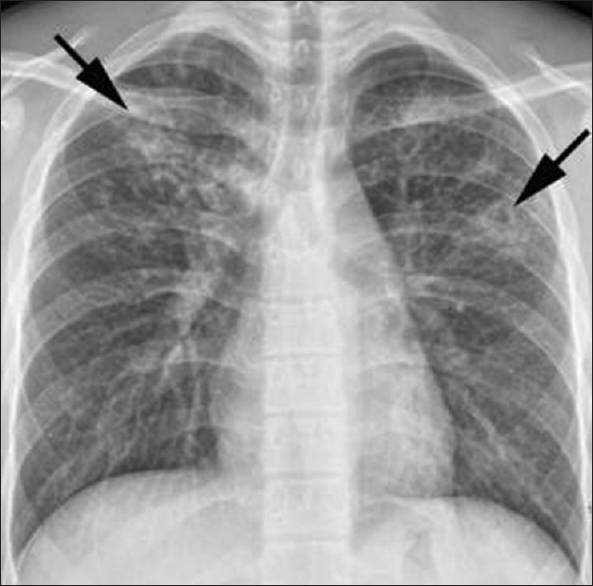

What may be seen on a chest x-ray for a patient with TB?